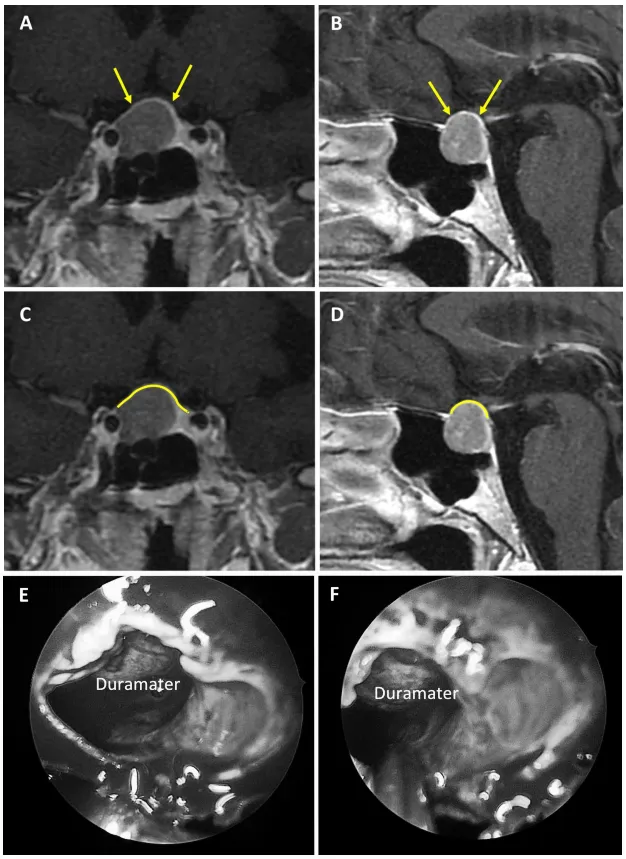

圖3

圖3:67歲女性無功能大腺瘤患者。a、b術(shù)前MRI:黃色箭頭指示厚度大于1毫米的強化屏障區(qū)。c、d術(shù)前MRI:黃色標記線標示強韌屏障位置。e、f術(shù)中圖像:可見由硬腦膜構(gòu)成的屏障結(jié)構(gòu)。

圖4

圖4:47歲男性生長激素腺瘤患者。a、b術(shù)前MRI:黃色箭頭指示厚度大于1毫米的強化屏障區(qū)。c、d術(shù)前MRI:黃色標記線標示強韌屏障位置。e、f術(shù)中圖像:可見由垂體腺構(gòu)成的屏障結(jié)構(gòu)。